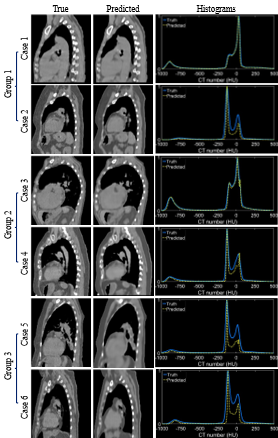

Fig. 3 depicts the violin plots to classify the evaluation results of patient images in three groups using k-means clustering[5, 29] based on MAE, PSNR, and SSIM. The figure includes probability distributions and interquartile ranges to measure the performance of the proposed method. The mean values of each metric show that the surface-volume network can generate 3D CT images with minimum uncertainty for patients in group 1 (Table 1). Fig. 4 shows the reconstructed volumetric images and ground-truth CT in transversal views for different cases from different groups. Fig. 4 also includes comparisons of SSIM, difference maps, and CT-number line profiles between synthetic images and ground truth. Fig. 5 illustrates the sagittal views of the reconstructed volumetric images, together with the ground-truth CT and histogram comparisons of CT numbers between generated images and ground truth. All evaluation metrics indicate the model potential regarding generating comparative volumetric images to 3D CT images acquired from treatment planning CT scanners. Indeed, the results indicates that the performance of deep hierarchical networks differs for patients in different groups (Fig. 3-5). The surface image datasets with high quality should increase the predictive capability as well as the learning efficacy, which potentially makes the surface-to-volume model deployable in the clinic.

Fig. 5. — Examples of predicted volumetric images from each group with histogram distributions of CT numbers. The sagittal views of ground truth and predicted CT are displayed. The training, validation, and testing datasets for each case include 1280, 160, and 160 CT images.